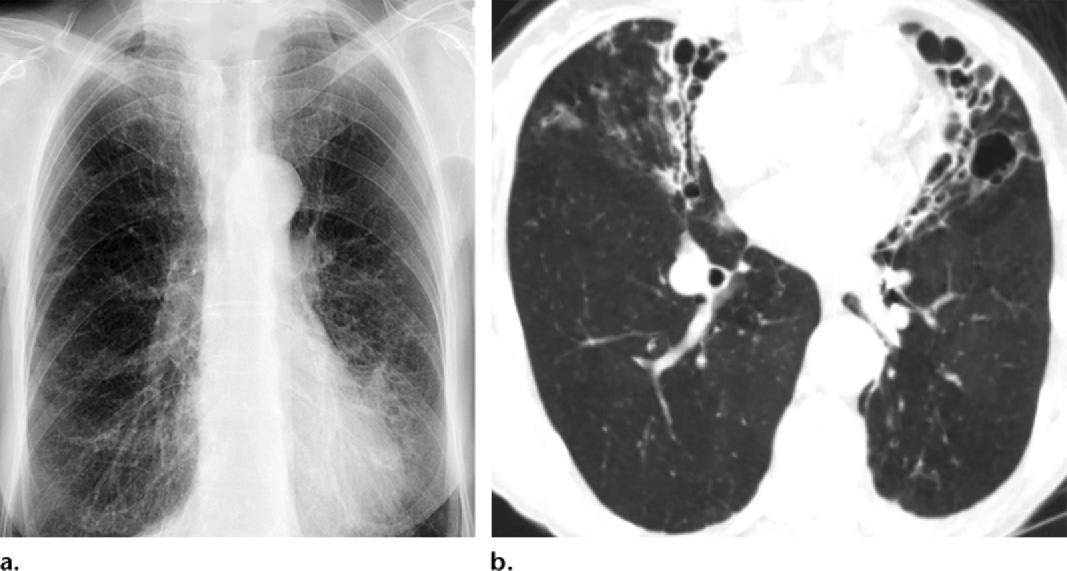

ct表现:支气管壁增厚和气道扩张4,其他表现:长期患病或反复继发感染可